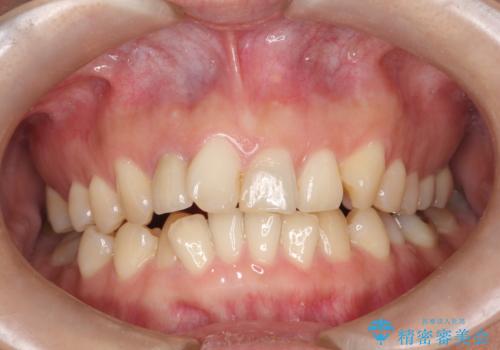

インビザラインで出っ歯を改善する 抜歯をしないinvisalign治療

- 20代女性

- 1年5ヶ月

- 非抜歯・遠心移動による前突の改善をマウスピースにて計画した。

非抜歯矯正の場合、大きく前歯を下げることはできませんが、奥歯の遠心移動や歯のサイズダウンにより歯軸を立て、見かけ上の出っ歯感をある程度改善することができます。